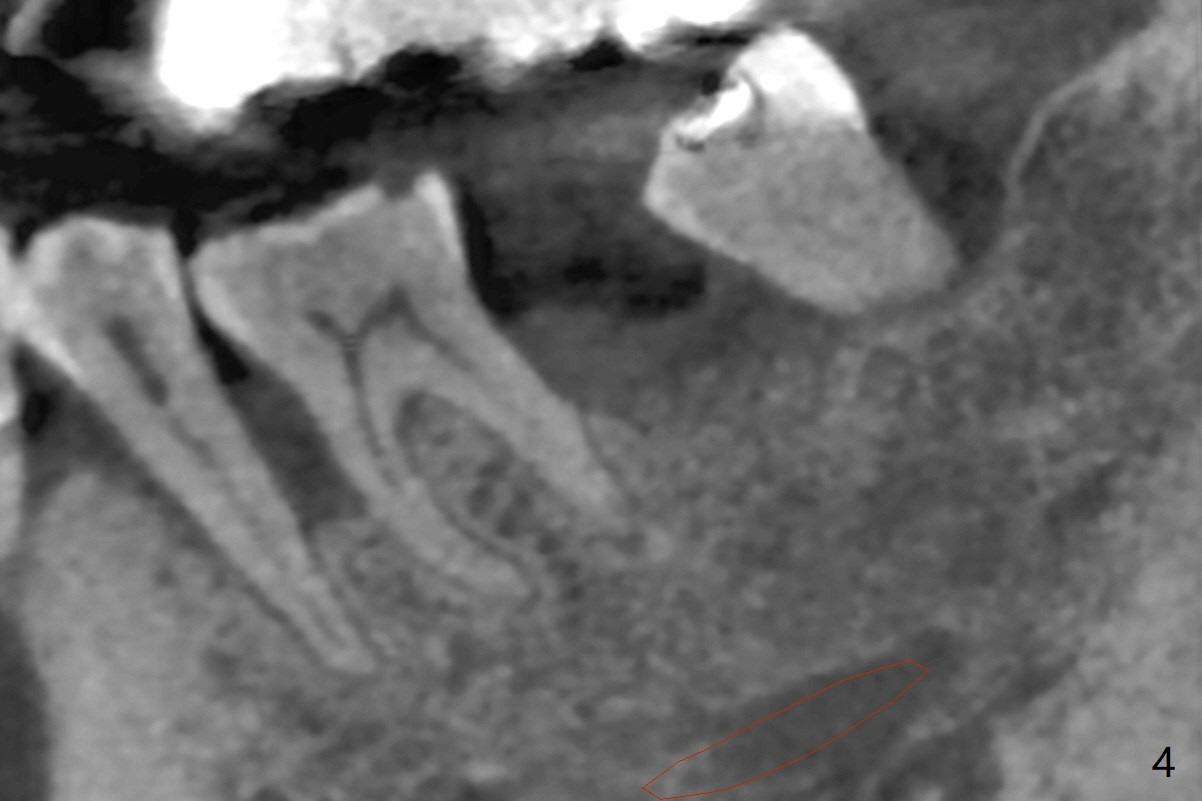

A 49-year-old man returns for #14 and 15 implant impression. The tooth #18 is buccally shifted with mobility, which is incompatible with #14 and 15 restoration. The tooth has to be extracted with socket preservation (Fig.1). A piece of 6-month collagen membrane is used to cover allograft. The socket is healing 9 days postop (Fig.2), probably related to its small wound. Three months and a half postop (Fig.3), CT shows bone healing (Fig.4 sagittal (thin) section, 5 (thick section); 6 (coronal (thin) section). A 5x8.5 mm implant will be placed (Fig.7,8).